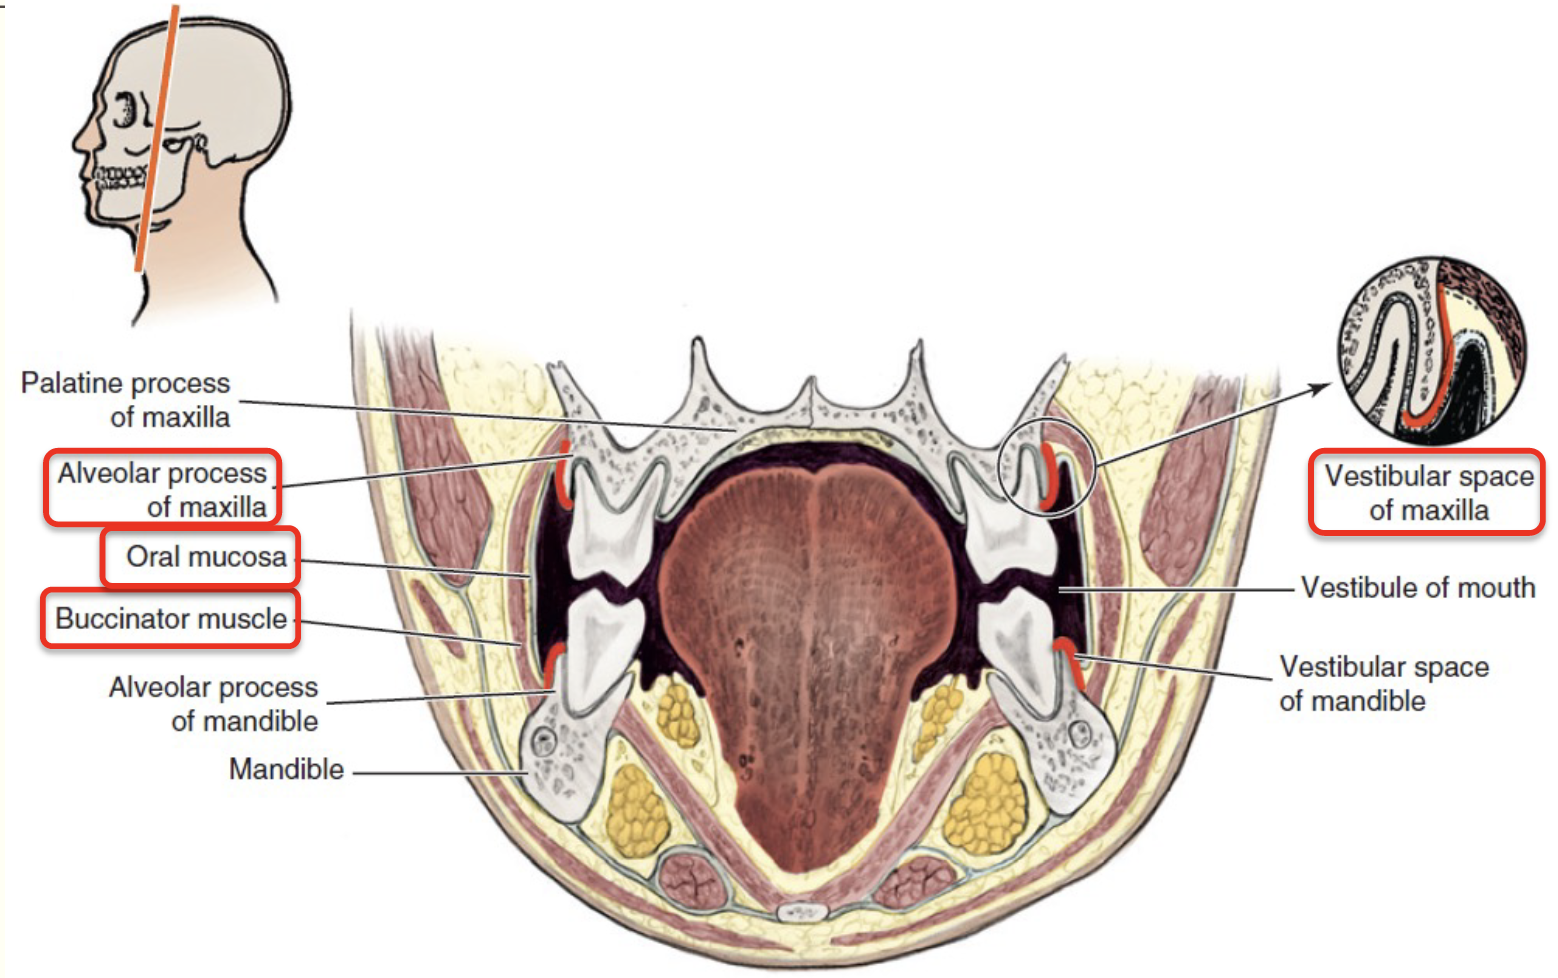

Space

Vestibular space

- of Maxilla

- of Mandible

Buccal space

- Buccal fat pad

- Parotid duct

- Facial a.